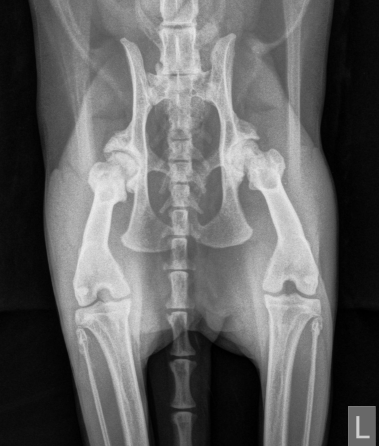

Durch die klinischen Symptome, den Bericht des Besitzers und unter Berücksichtigung des Alters hat Ihr Tierarzt häufig schon einen starken Verdacht. Dieser lässt sich durch die Röntgendiagnostik bestätigen und liefert Hinweise auf den Schweregrad der Erkrankung.

Eine gezielte Röntgenuntersuchung zeigt in der Regel das Ausmass der Arthrose in den betroffenen Gelenken. Leider sind diese Veränderungen nicht heilbar. Das Ziel einer Therapie ist die Verminderung der Schmerzen und die Verbesserung der Gelenkbeweglichkeit.